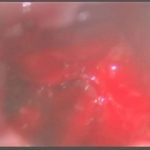

術中写真

摘出 中